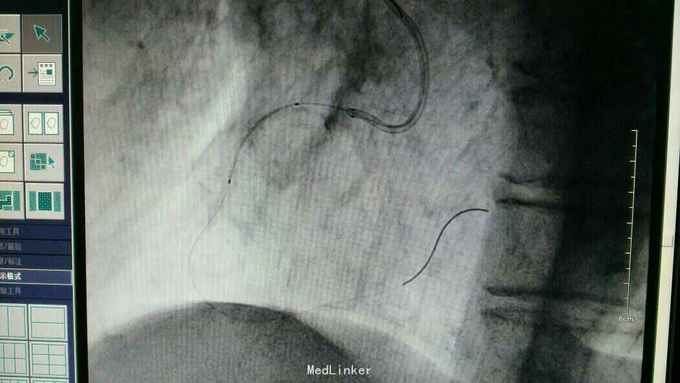

急性下壁心肌梗死,立即启动绿色通道,行急诊冠脉造影明确冠脉病变,必要时PCI治疗,行CAG示:LAD中重度狭窄,LCX尚可,RCA中段局限重度,可见前向血流,选段后降支处重度狭窄,血管钙化明显。考虑此次靶血管为RCA中段处,血管钙化迂曲明显,拟处理RCA,术中导丝到达远端后,预扩球囊反复高压扩张后,支架均无法通过,采用双导丝增加支撑依然无法通过,再更换高压后扩球囊高压扩张,锚定等,最终成功植入支架

急性心梗有时候处理相对较容易,但此病变在于血管钙化迂曲明显,且再次详细阅片后发现局部有“礁石”样病变,预扩球囊及后扩球囊不易扩张,有时需切割或旋磨,但对于急性心梗,如果血流达到理想级别,可不勉强处理,急性心梗中,有些病变为固定狭窄基础上急性血管闭塞,处理并非如一般血栓病变那样容易,造影后仍然需要详细阅片,根据具体病变情况选择合适手术处理方法